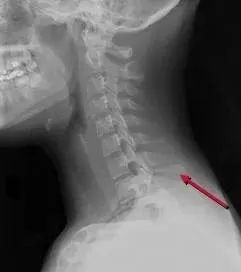

九、韧带损伤

多由屈曲性损伤导致,椎间隙前窄后宽,棘突间距增宽,椎小关节间隙增宽,50%伴有椎体滑脱;85%伴有神经功能损伤。